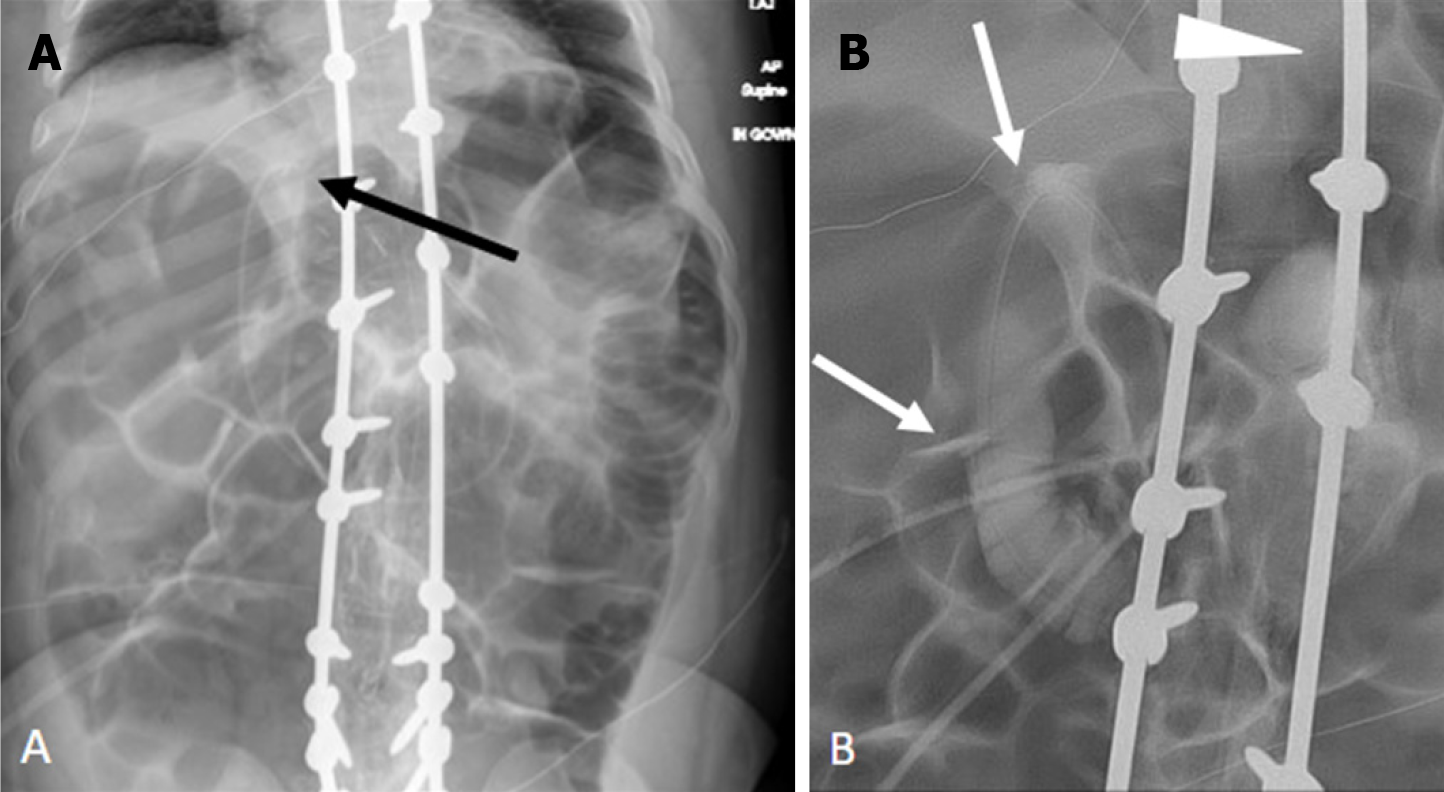

Figure 8 Retraction of gastrojejunostomy tube into the stomach identified incidentally on scoliosis radiographs.

A: Frontal; B: Lateral spine radiographs. They show retraction and coiling of the gastrojejunostomy tube (arrows) into the stomach without a retroperitoneal course; C: Frontal abdominal radiographs of the same patient 10 days prior demonstrates gastrostomy tube coursing normally along the C-loop of the duodenum (arrowhead).